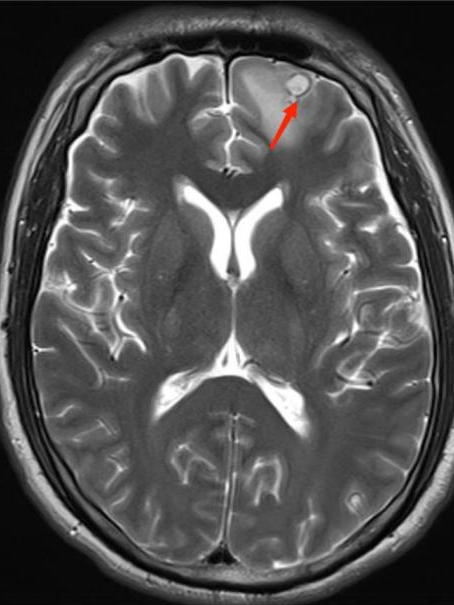

得到这条线索后,ICU 医生立即为李先生进行一系列脑部检查。最终,李先生头颅 MR 显示其脑内有寄生虫感染!明确诊断为脑囊虫病!